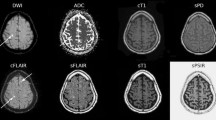

All T2-FLAIR was scanned on a 1.5-T scanner (Magnetom Avanto; Siemens Healthineers). The scan times were 128 s for conventional T2-FLAIR, 45 s for EPI-T2-FLAIR, 74 s for ETL-T2-FLAIR, and 79 s for TR-T2-FLAIR. The detailed scan parameters for the conventional and fast T2-FLAIR were as previously reported6 and are listed in Table 3 and representative images are presented in Fig. 4.

Acute and chronic ischemic hyperintensities on conventional T2-FLAIR and fast scanned T2-FLAIR with respect to DWI. (a) First group with conventional T2-FLAIR, EPI-T2-FLAIR, and ETL-T2-FLAIR. (b) Second group with conventional T2-FLAIR, ETL-T2-FLAIR and TR-T2-FLAIR. DWI diffusion-weighted image, FLAIR fluid attenuated inversion recovery, EPI echo-planar imaging, ETL echo train length, TR repetition time.